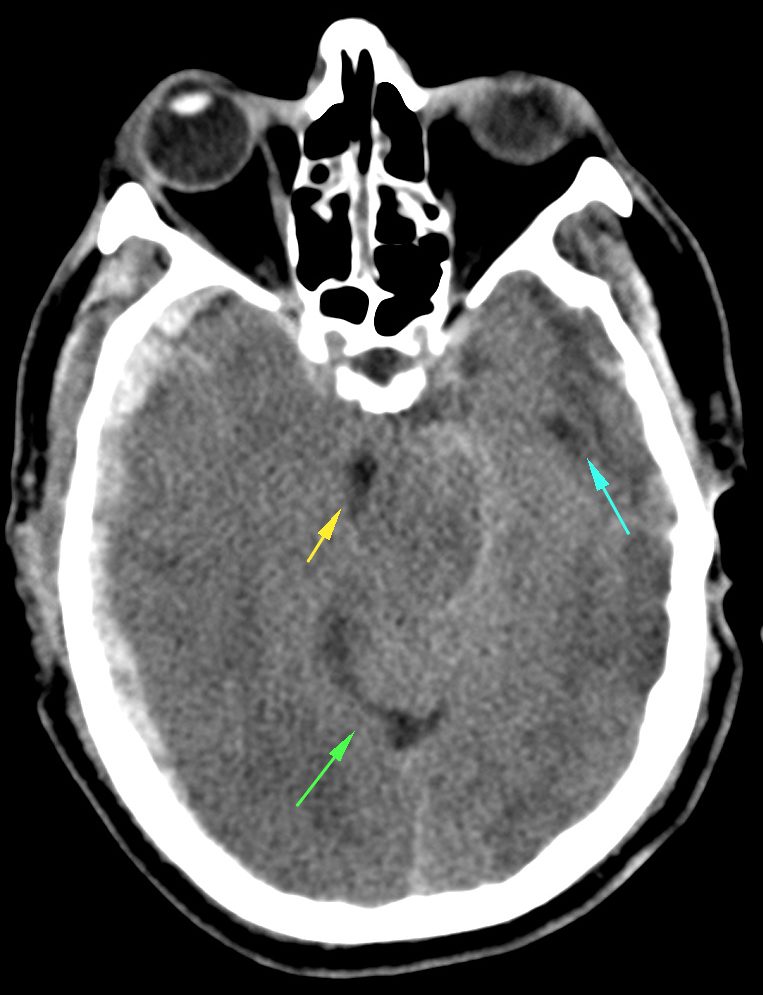

Subfalcina:

- Se produce la herniación de la circunvolución del cíngulo a través de la hoz.

- Puede producir compresión del asta y atrio del ventrículo ipsilateral.

- El VL contralateral puede dilatarse por obstrucción del agujero de Monro.

- Infartos del territorio anterior por compresión de la ACA y venas profundas.